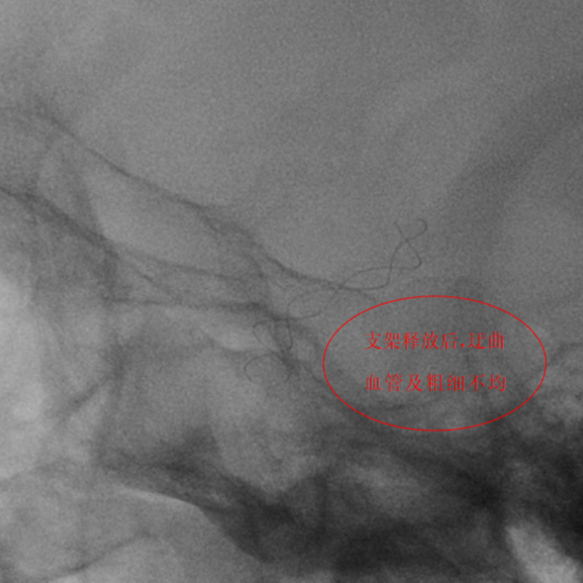

第二例患者为左侧大脑中动脉动脉瘤,该部位血管解剖结构复杂,对手术的精准度要求极高。团队使用血流导向装置,支架完美打开及贴壁,患者术后3天顺利出院。